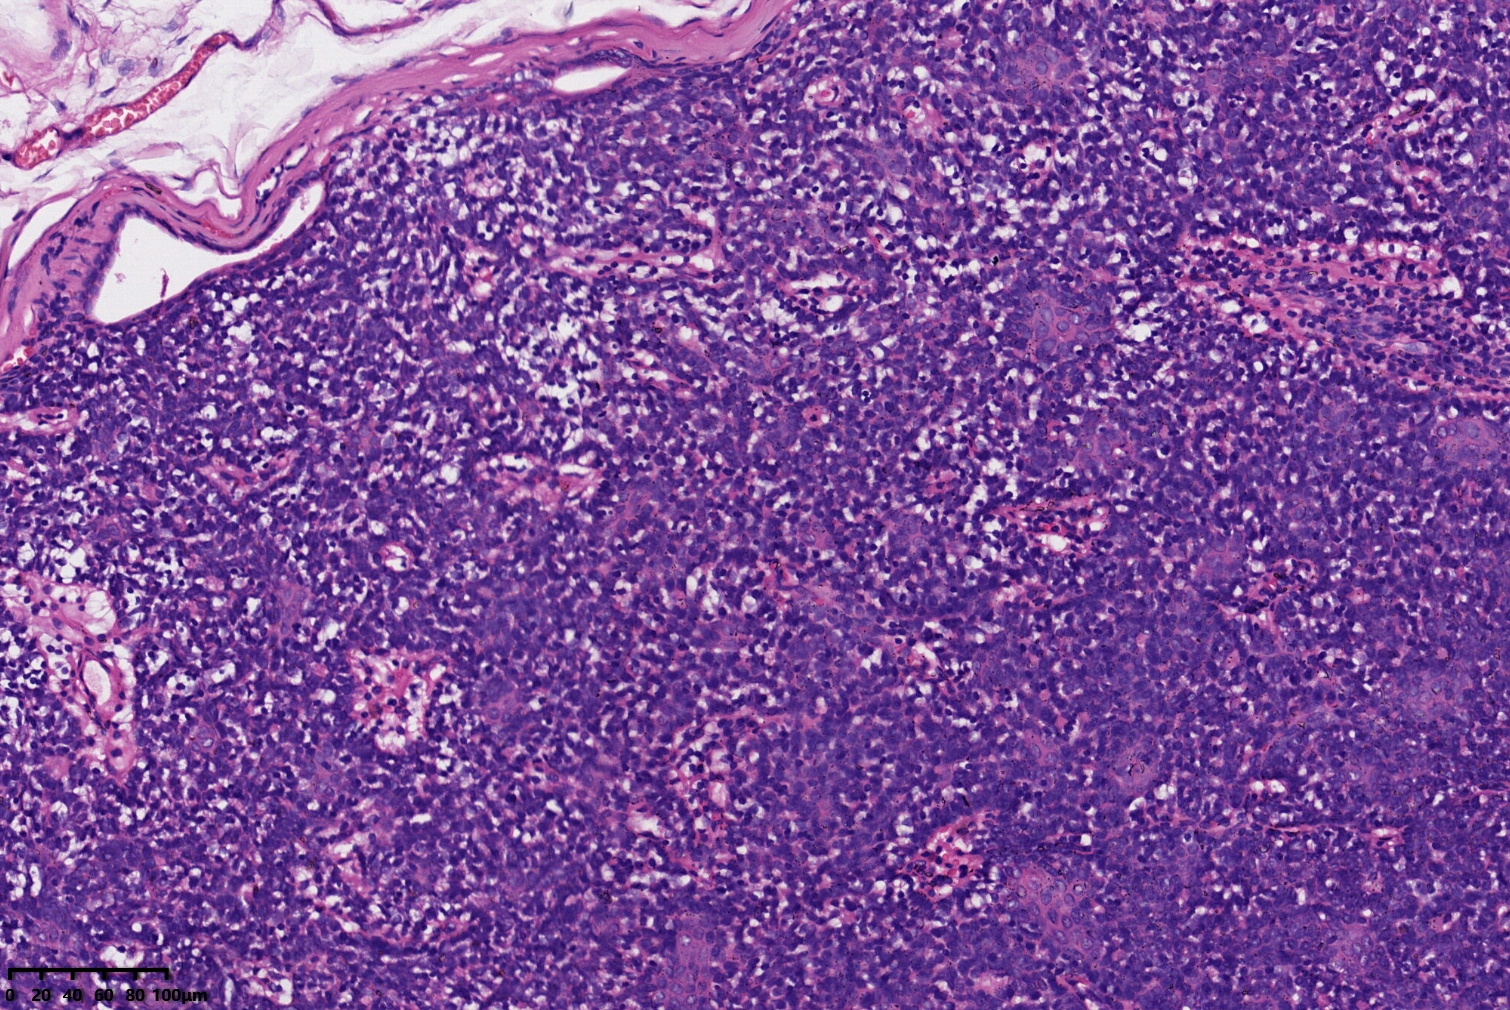

汗腺腺瘤?

背部包块

同意,有的区域像透明细胞汗腺瘤

小汗腺螺旋腺瘤